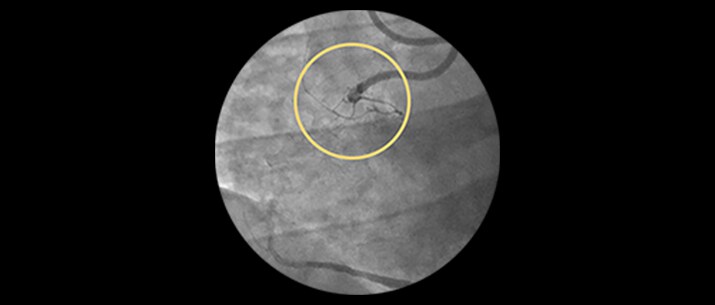

ELCA Success and safety rates

| Study | Lesion type | Technical success | Procedural success | MACE Rates* |

| Bilodeau | Calcified and complex coronary lesions | 92.0% | 93.0% | 8.0% |

| | Calcified, uncrossable, resistant coronary lesions | 95.5% | 95.5% | 8.0% |

| Pratsos | Crossable coronary lesions | 98.1% | 99.0% | 0.0% |

*Total occlusions traversable by a guide wire.